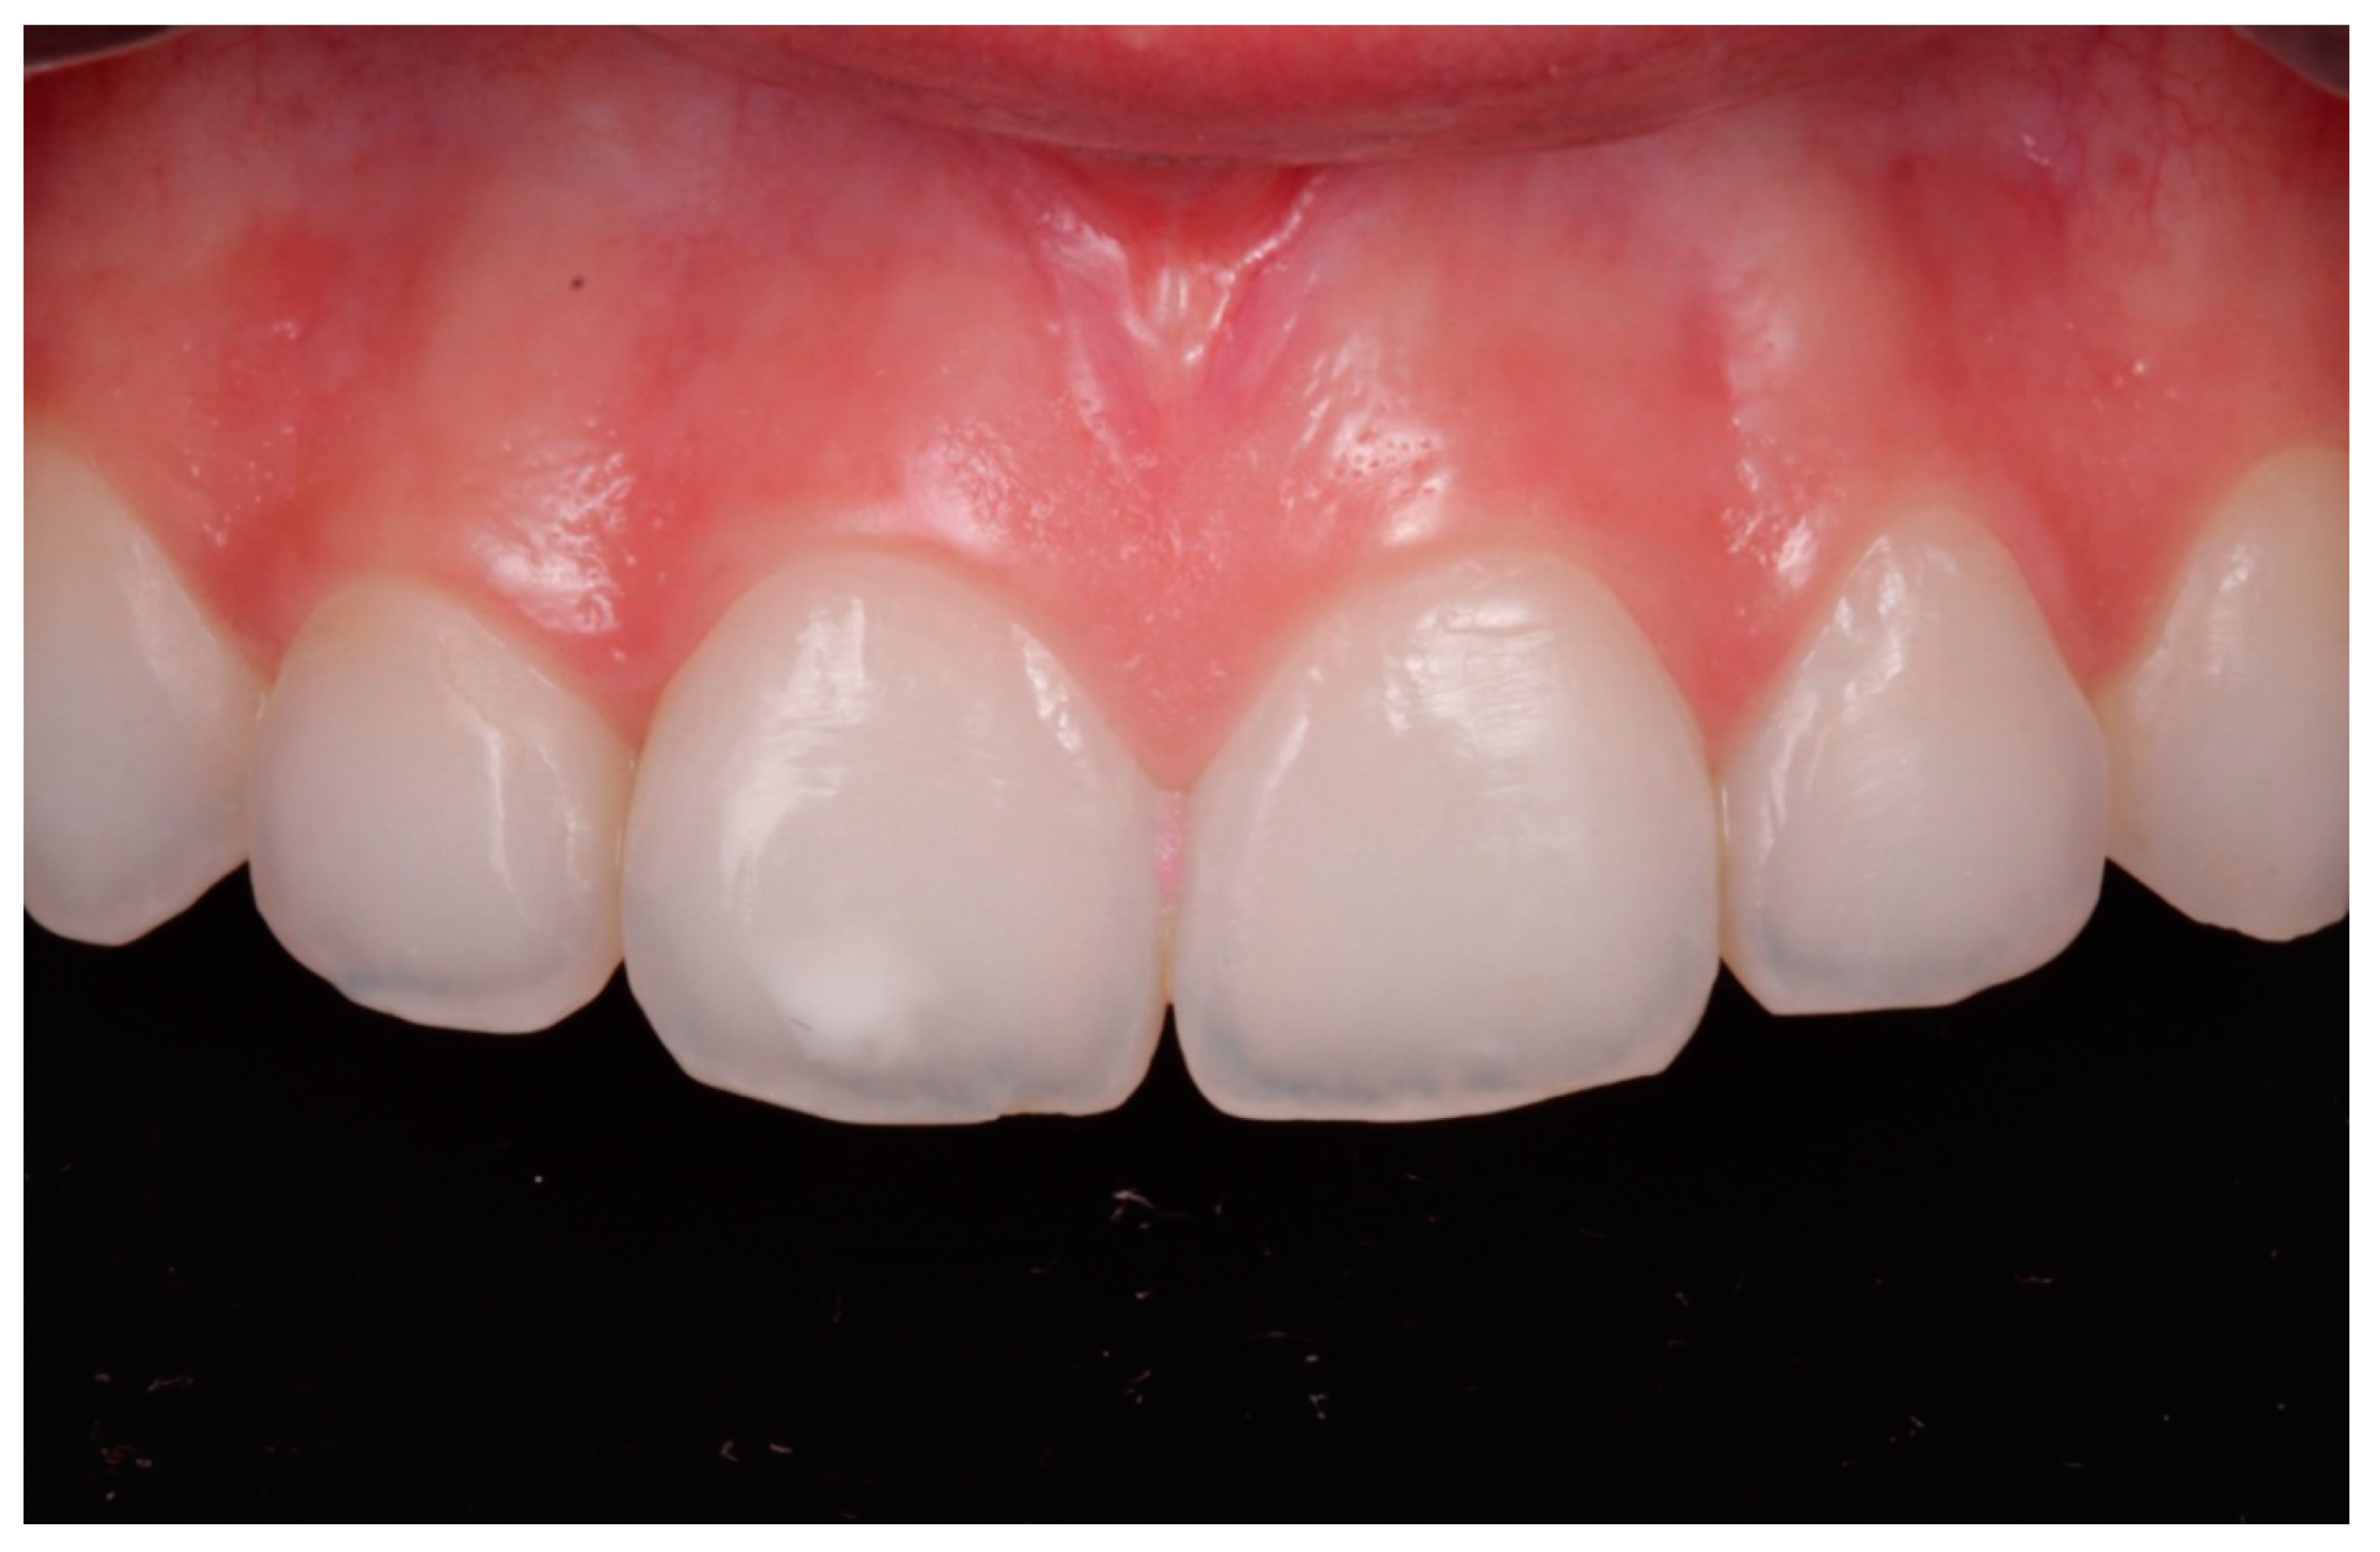

- In cases where the 15% HCl product was applied (ICON etch; DMG), each affected tooth received three applications of chemical erosion treatment for two minutes each. The product was placed with the tip of a sponge applicator on the enamel surface for 2 min. When 2 min had passed, the enamel was washed with abundant water for 30 s (Figure 1, Figure 2 and Figure 3).